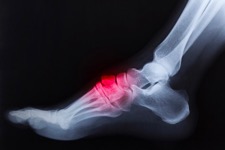

Radiografia comparativa dei pedi, di una paziente caduta accidentalmente , mentre era in punta di piedi. Si noti come le articolazioni del medio piede di sinistra siano dislocate.